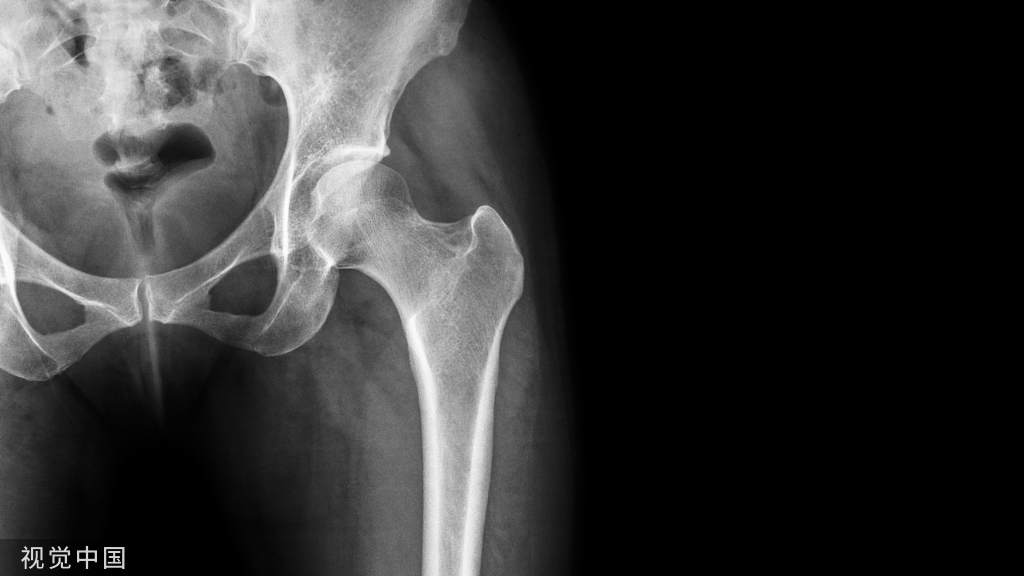

关于HO的发生率,多数研究报道为10%~20%。无论是中枢神经损伤性还是四肢创伤性HO,最好发是髋关节,其次是肘、膝、肩,几乎不累及腕、踝、手、足这样的小关节。

脊髓损伤患者的HO极少发生于上肢关节。创伤性HO可位于关节旁或将关节包绕,而神经损伤性HO则往往位于关节旁。在创伤骨科中,尤以髋臼骨折和肘关节骨折最为多见。关节置换术后以及严重的长骨骨折后异位骨化发病率为3%~20%。